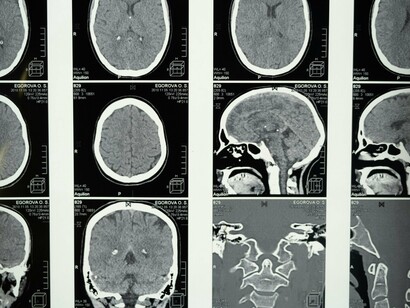

O diagnóstico correto entre tremor essencial e tremor parkinsoniano é crucial para o manejo adequado. Além da avaliação clínica detalhada, os neurologistas podem utilizar:

Testes de função neurológica.

Exames de neuroimagem, como ressonância magnética, para descartar outras causas.

Em alguns casos, exames de medicina nuclear, como SPECT ou PET, para avaliar a função dopaminérgica no cérebro.

Testes genéticos, especialmente em casos de início precoce ou forte história familiar.

É importante notar que, em alguns casos, o diagnóstico pode não ser imediatamente claro, e o acompanhamento ao longo do tempo pode ser necessário para estabelecer um diagnóstico definitivo.